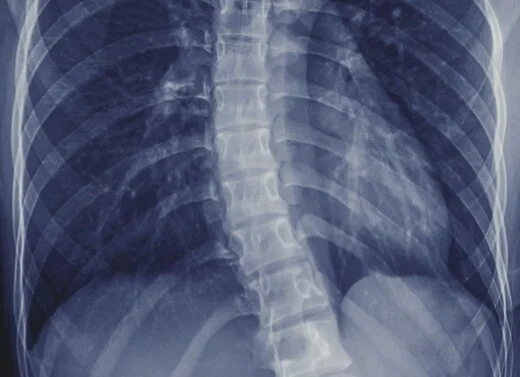

Wirbelsäulengymnastik mit Skoliose

Unter der Annahme einer biomechanischen Ursache der Wirbelsäulenverbiegung bei idiopathischen Skoliosen werden zahlreiche gymnastische Behandlungen empfohlen, die dem Fehlwachstum begegnen sollen. Weltweit werben spezialisierte Skoliosekliniken mit intensiven Programmen, die das Fortschreiten verhindern und die Operation vermeiden sollen.

Die Skoliose steckt in uns allen - das wussten die alten Anatomen sehr gut und bekannten, dass sie völlig gerade Wirbelsäulen nur bei Tieren gefunden hätten, aber niemals bei Menschen! Genaue Vermessungen der Wirbelkörper finden Verbiegungen der Wirbelkörper von ca. zwei Winkelgraden auch bei offensichtlich völlig geraden Wirbelsäulen.

Lange weiß man auch, dass die Skoliose irgendwie mit dem aufrechten Gang zusammen hängt, aber wie genau das funktioniert ist ein ungelöstes Rätsel. Beständig wird auch behauptet, die Skoliose zeige eine Rotation (=Achsdrehung). Das ist falsch, weder die Wirbelkörper noch die angrenzenden Strukturen (Gefäße, Nervenbahnen, Rückenmark) zeigen eine Rotation.